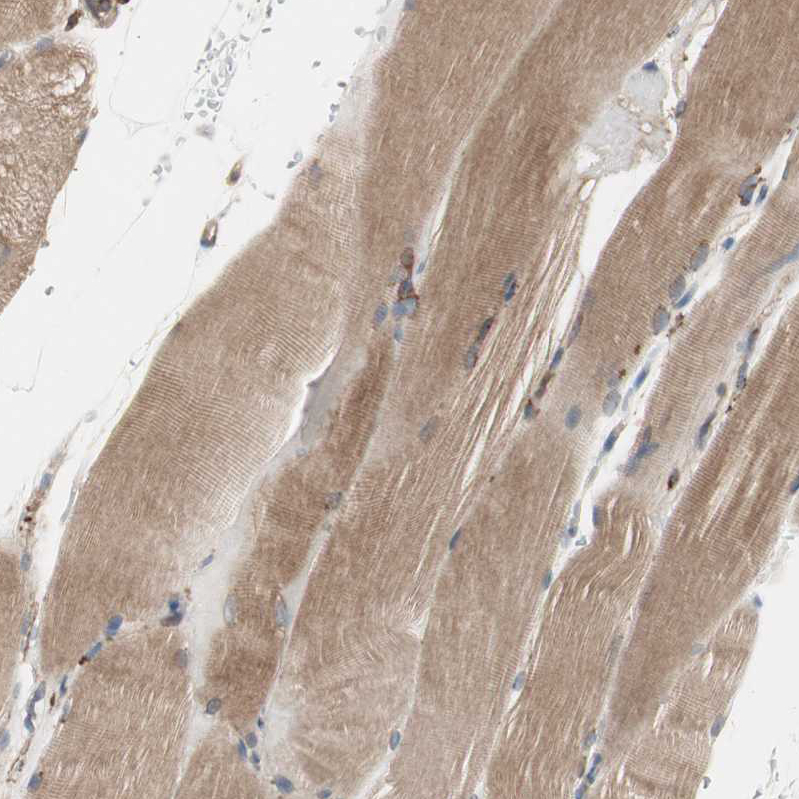

Immunohistochemical staining of human skeletal muscle shows moderate cytoplasmic positivity in myocytes.